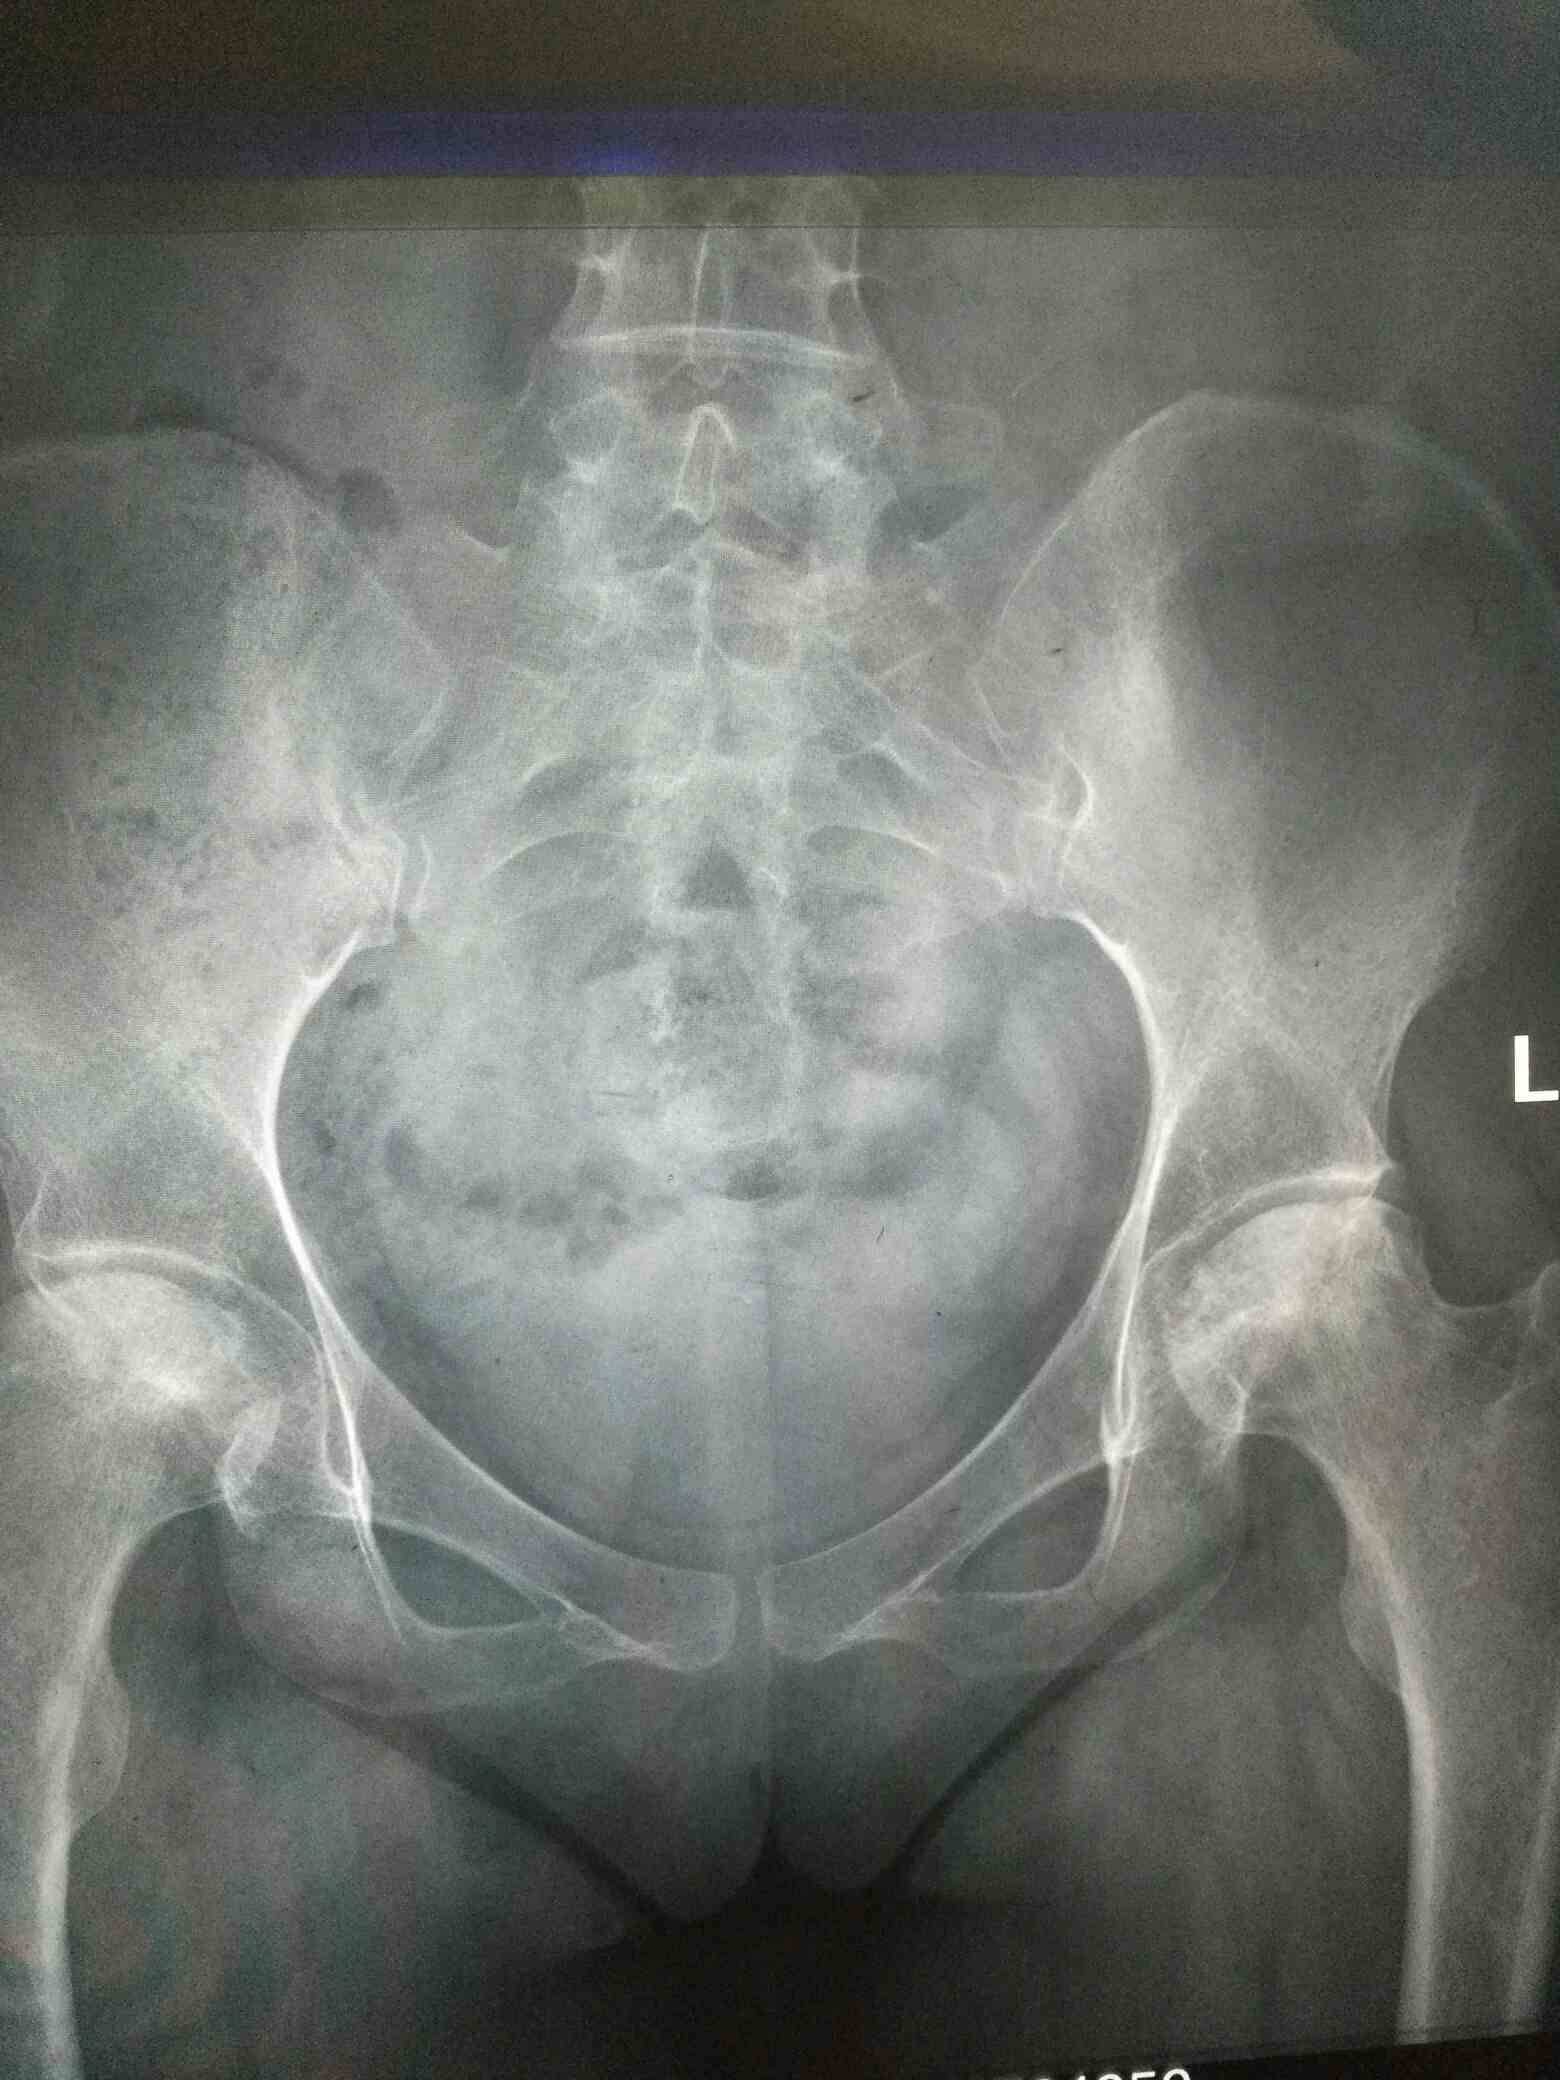

骨坏快两年了,昨天也拍了片,和原来拍的片对比了一下,也没有发展,看来坚持泡脚搓腿还是有效果的,真的很高兴。